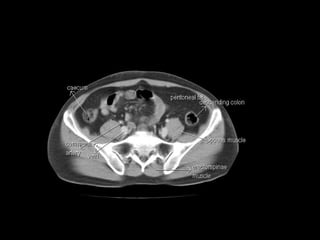

Radiographers use medical imaging equipment like X-rays and MRIs to produce images of patients' internal structures and organs. They are responsible for positioning patients, operating scanning machines, and ensuring quality images. Radiographers must have strong attention to detail, excellent communication skills, and the ability to work well under pressure to accurately capture anatomical features and diagnose any abnormalities.